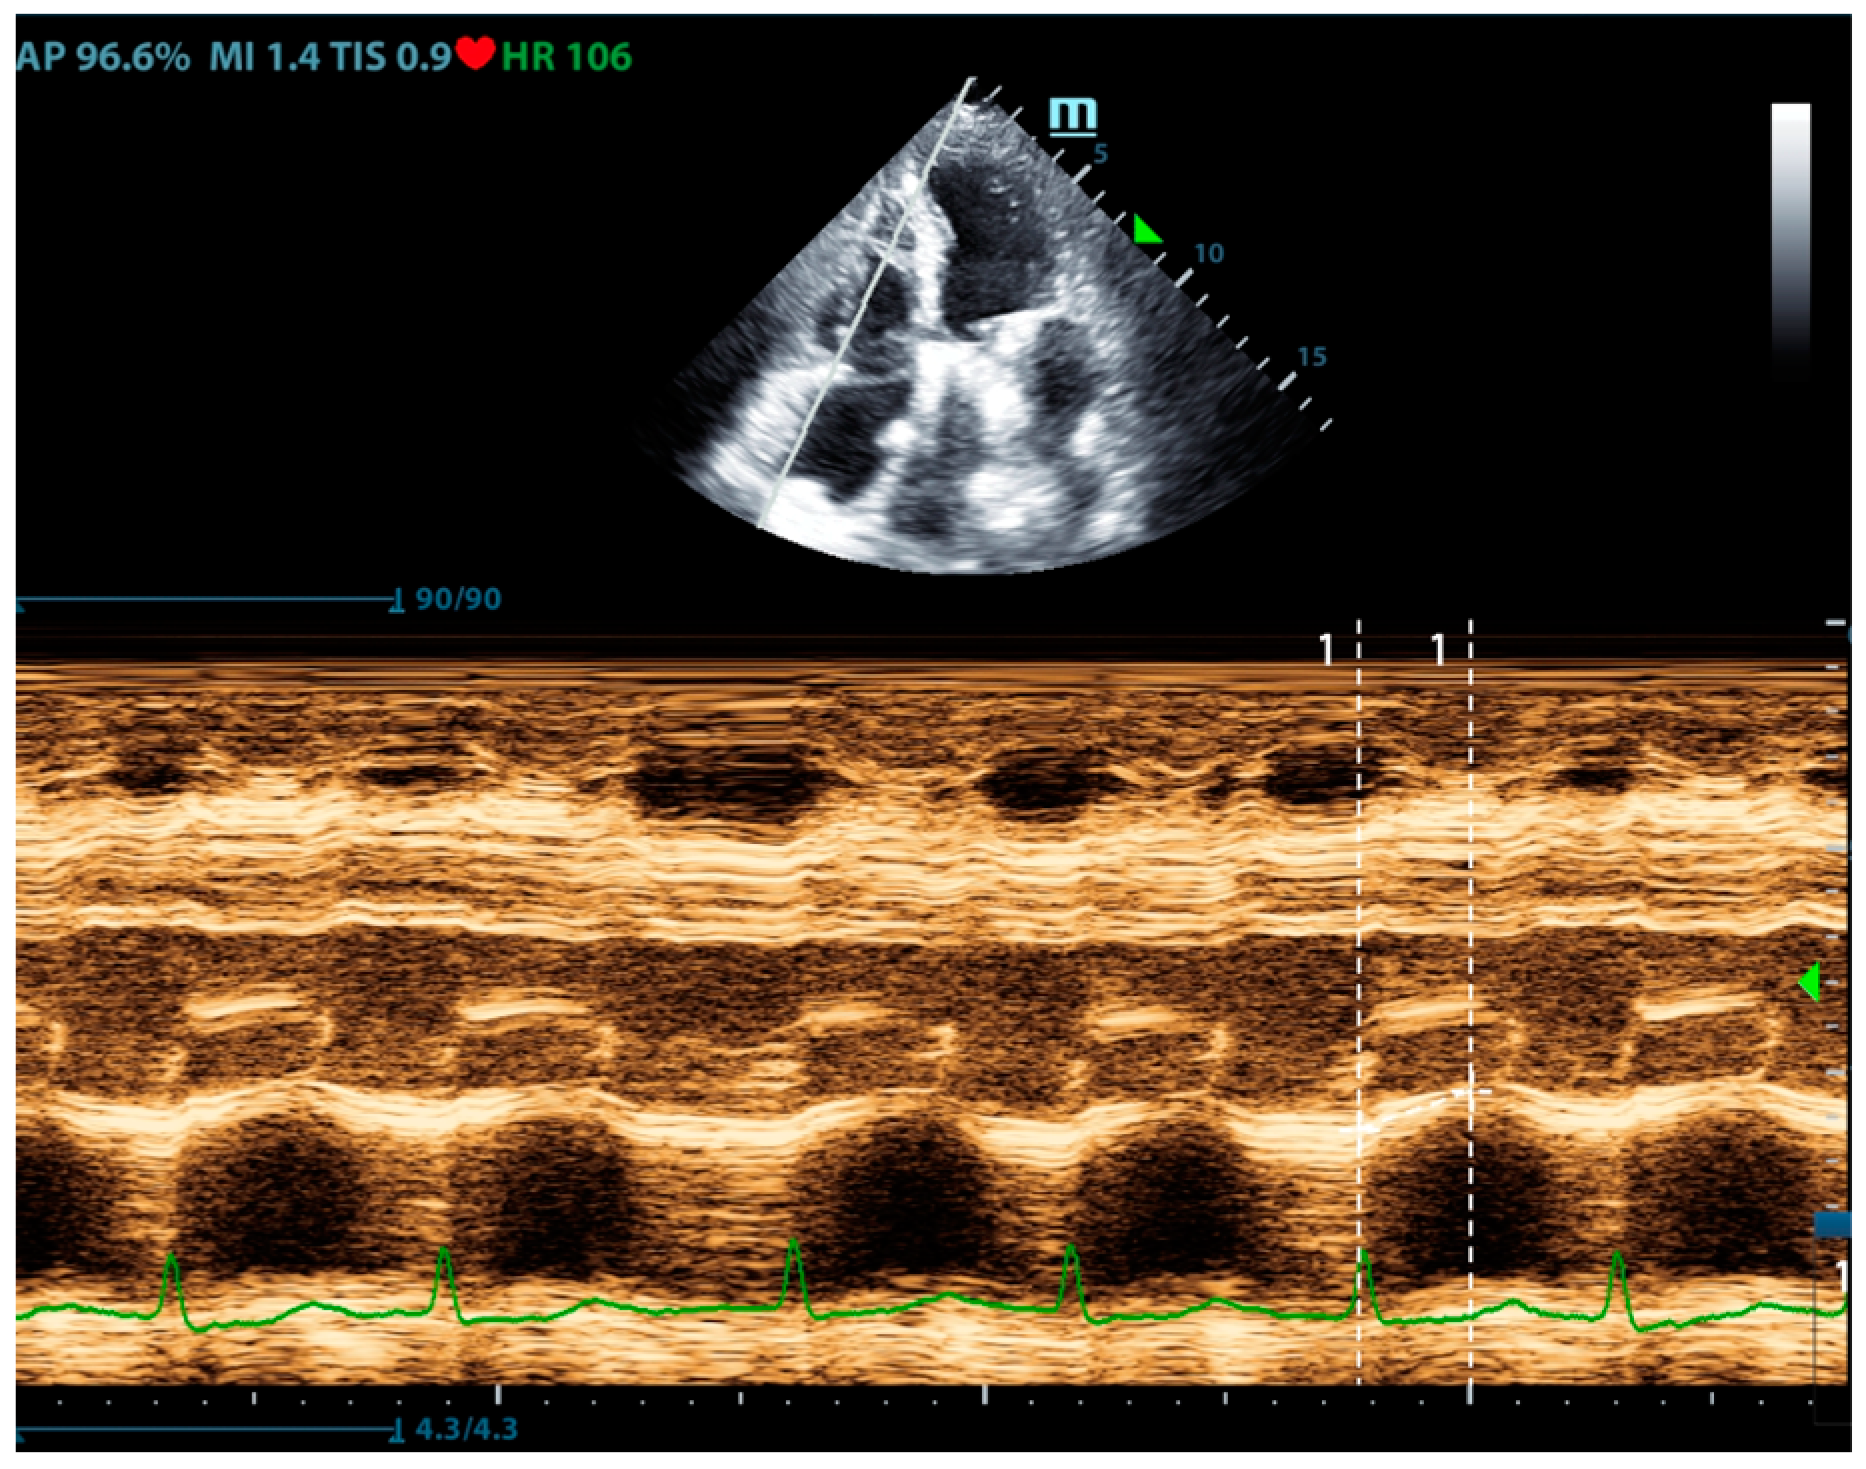

Right ventricular systolic function is an important part of pulmonary circulation assessment. Compared with the left ventricle, which mainly performs a concentric and twisting motion, the contraction of the right ventricle is mainly a long-axis contraction. Therefore, the assessment of right ventricular long-axis systolic function can reflect the overall right ventricular systolic function. Tricuspid annular plane systolic excursion (TAPSE) is the most used indicator to reflect the long-axis contraction of the right ventricle (Figure 4). A TAPSE less than 16 mm indicates right ventricular systolic dysfunction [20]. Although it reflects the longitudinal systolic function, it is well correlated with other indicators that reflect right ventricular systolic function (such as RVEF and RVFAC) [21,22]. Comparing these parameters, TAPSE is most widely used in right heart systolic assessment for its feasibility and reliability. In addition, the systolic peak flow velocity S’ of the right ventricular free wall can also reflect the systolic function of the right ventricle. Tissue Doppler measurement is performed at the base of the right ventricular free wall, and S’ < 10 cm/s indicates right ventricular systolic dysfunction [23,24]. However, this method has poor measurement repeatability for segmental dysfunction and lacks reference values for all age groups, especially the elderly, so it was currently used as a research tool.

Figure 4.

The ultrasound measurement of TAPSE.

In the long-axis view of the pulmonary artery, physicians can measure the velocity-time integral (VTI) of the right ventricular outflow tract (RVOT). As well as LVOT-VTI, RVOT-VTI is strongly associated with stroke volume and can predict low cardiac output and poor outcomes [25]. The use of RVOT-VTI as a surrogate indicator for cardiac output evaluation by point-of-care ultrasound can be considered in cases where accurately measuring LVOT-VTI is challenging (e.g., patients with aortic valve disease). However, obtaining the necessary views and appropriate measurement angle requires experience; this limits the application of RVOT-VTI in critical care and emergency settings.